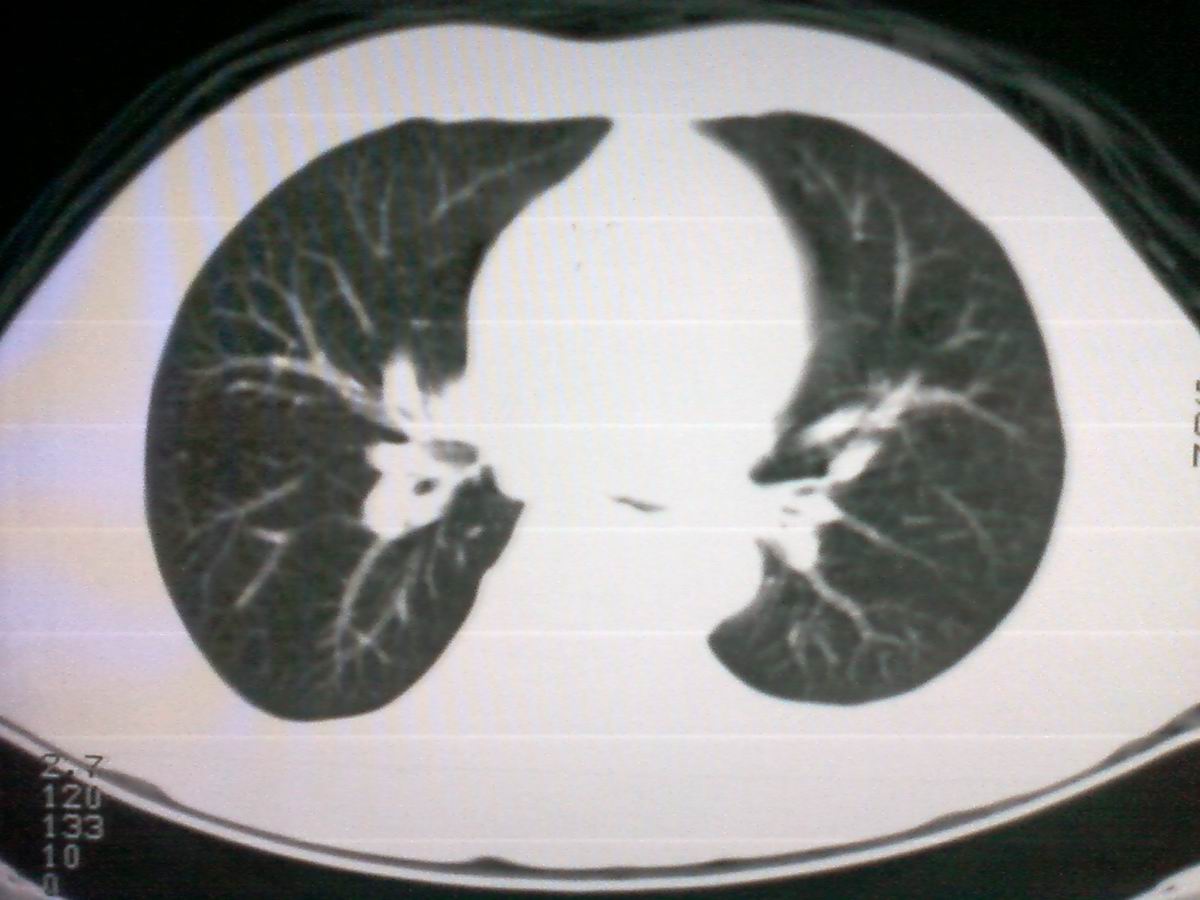

标题: CT25801:患者男性,65岁,临床提示双肺可闻及广泛罗音,看 [打印本页]

标题: CT25801:患者男性,65岁,临床提示双肺可闻及广泛罗音,看

仅见肺纹理影增重 纵膈淋巴结钙化

支持气管内恶性肿瘤,建议支气管镜活检。

支管占位,建议作支纤镜检查及活检。